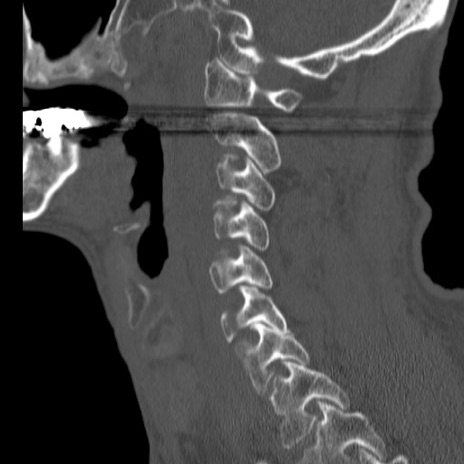

症例46 頚椎CT(矢状断像)

【症例】80歳代男性

【主訴】両側頚部〜上肢のしびれ

【現病歴】昨日、自宅内で転倒、その後より上記症状あり。意識障害なし。

【身体所見】両側上肢のallodynia(熱痛覚過敏)あり。MMTおよびDTRは正確な所見取れず。両上肢の挙上はなんとか可能。

異常所見と診断は?